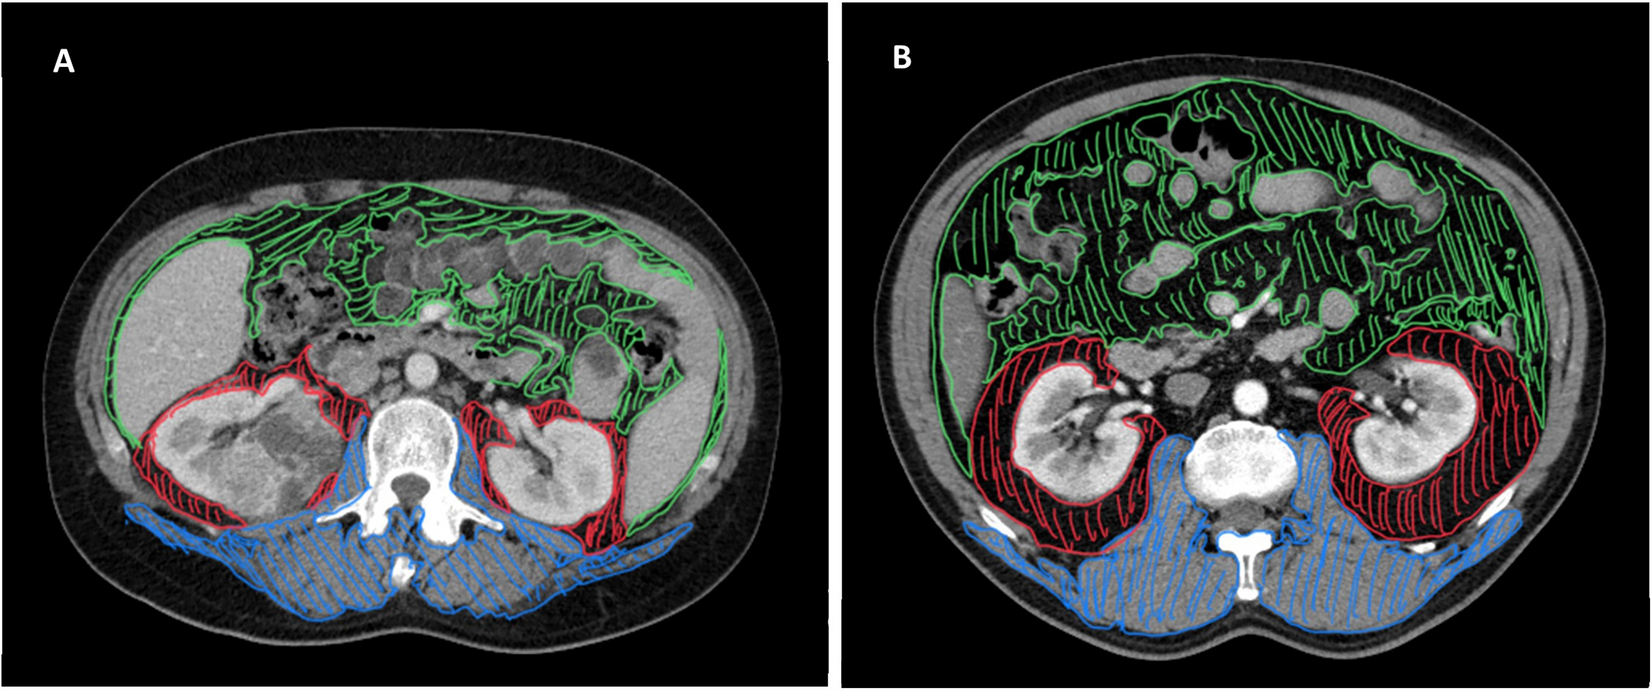

Figure 5

Representative examples of adiposity measures using CT scan. Axial images at the level of renal hilum from a non-obese (A) and an obese patient with RCCa (B). VAT is represented in green, PRAT in red and skeletal muscles in blue. VAT, visceral adipose tissue area; PRAT, perirenal adipose tissue; CT, computed tomography.